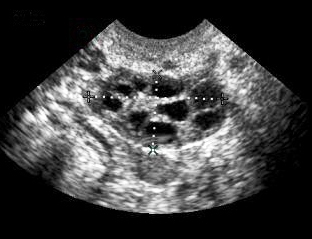

Така изглеждат и двата ми яйчника!

- pcos_us.jpg (49 KiB) Прегледано 3119 пъти